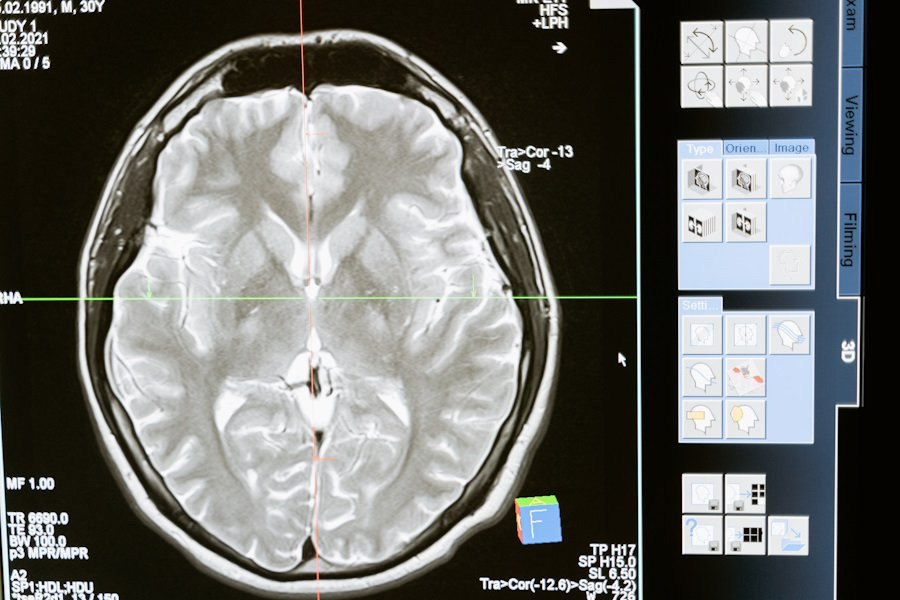

Результаты этого исследования опубликованы на портале Nature. Исследователи использовали внутричерепную электроэнцефалографию (ЭЭГ) для наблюдения за активностью мозга у участников эксперимента.